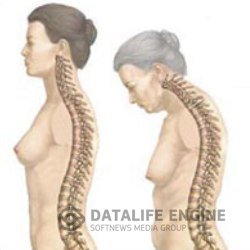

Болезнь БехтереваЭтот недуг считают неизлечимым. Его вызывают дисфункция почек, неполадки в желчном пузыре и печени, протоки... Болезнь БехтереваЭтот недуг считают неизлечимым. Его вызывают дисфункция почек, неполадки в желчном пузыре и печени, протоки...